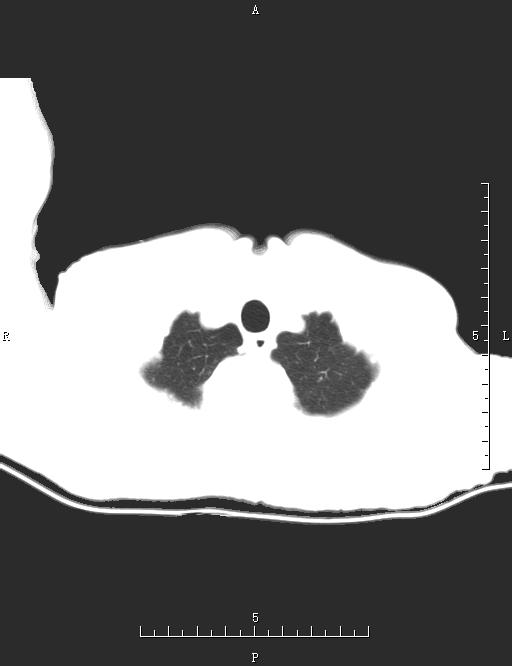

CT52575:胸部CT

本帖最后由 cefcmj 于 2017-1-23 18:59 编辑 男,58岁,反复咳嗽、咳痰10余年,加重3天。

左上肺可见团块状斑片状密度增高影,内见透光区及支气管气相,灶周模糊,左下肺胸膜下少许索条影,右下肺小圆形透亮影,考虑:左上肺感染性病变-----肺脓肿可能性大。左下肺少许慢性炎症。右下肺大泡。

两肺内可见细小点状影,右上肺及左肺下叶背段可见斑片索条影,左下肺见小圆形低密度透亮影,纵膈内可见肿大淋巴结。肝内胆管扩张。考虑:两肺继发性结核并支气管播散,左下肺大泡。肝内胆管扩张。

考虑:继发性肺结核,伴支气管感染,不除外急性血型播散。

右肺细支气管肺泡癌不排除,建议消炎治疗后复查。另:纵膈淋巴结肿大。